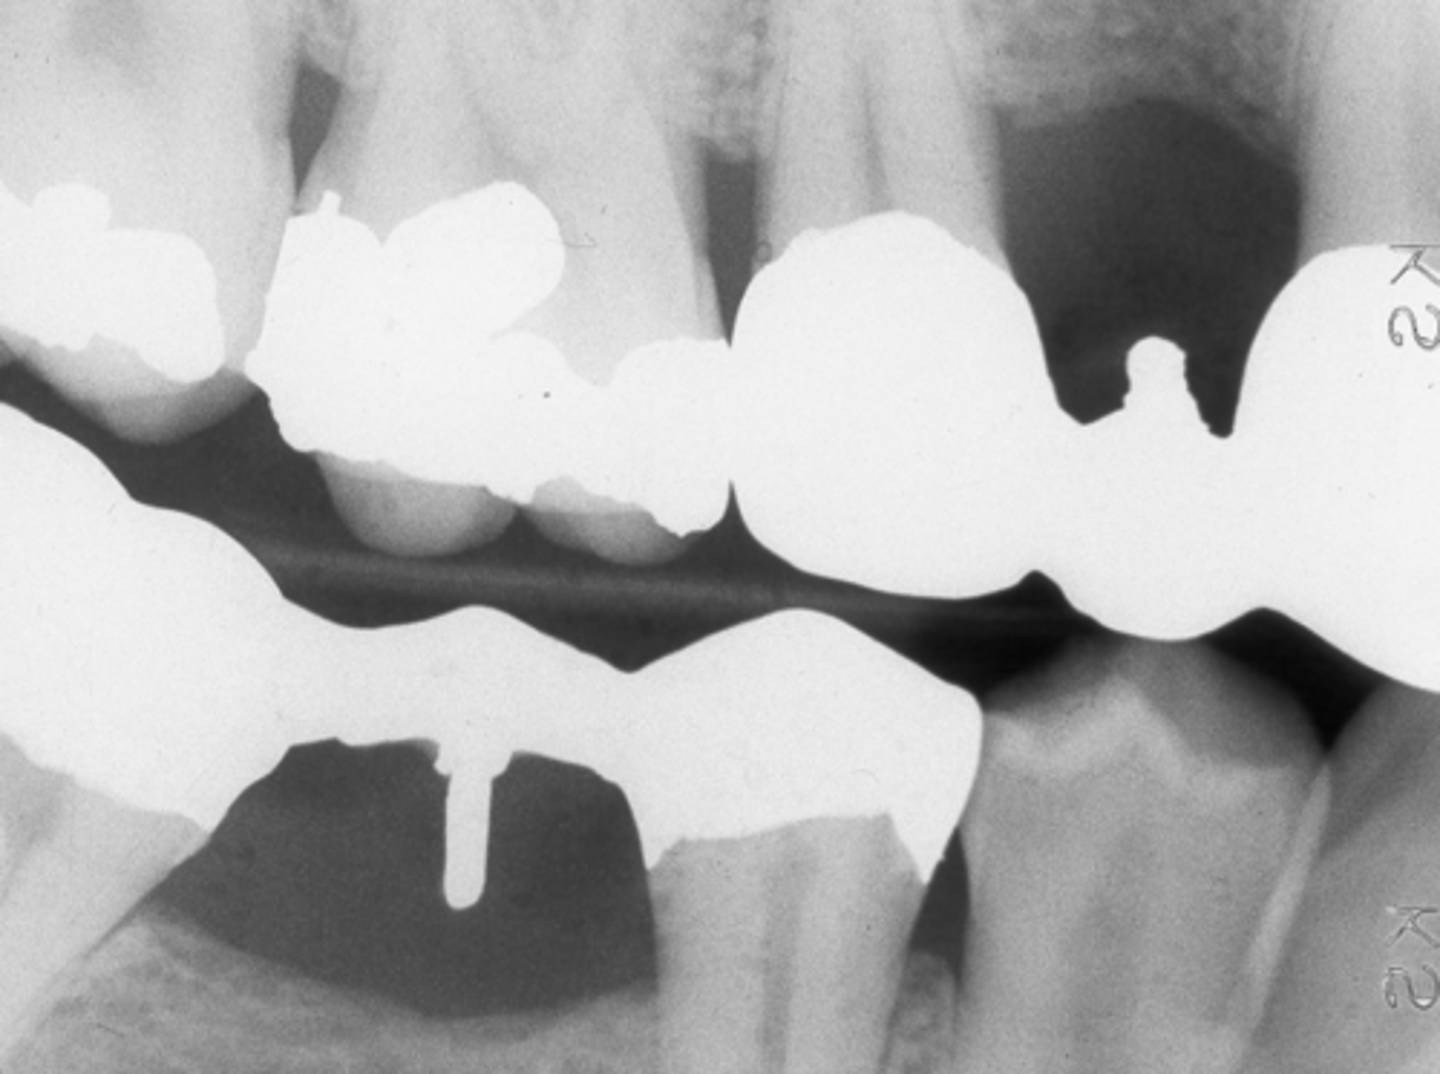

Gold restorations

Radiopaque

- Gold crowns and bridges

- Gold inlays and onlays

- Gold foil restorations - usually occlusals or cervical

Gold crowns, amalgams example

Gold restorations examples

- Gold crowns and amalgam restorations and onlay